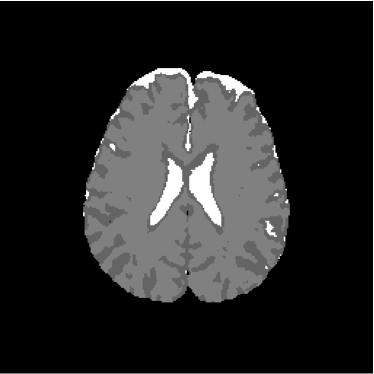

Figure 28 shows 13th slice of classification result obtained by the use of the objective dialectical classifier. Figure 29 exhibits 13th slice of classification result after performing post-labeling, whilst figure 30 shows the entire volume generated by ODC classification.

The training process of ODC algorithm resulted in 6 classes. These classes were reduced to 4 after manual post-labeling, merging 3 classes out of brain region, namely image background, noise and cranial box. The post-labeling is manual because all 3 cited regions are statistically different and, consequently, they are merged due to our interest in classes more related to the brain regions. On figure 29 it is possible to notice that ODC was able to distinguish white matter from the gray matter present in the interface between liquor and white matter.

Refer to caption

Figure 28: 13th slice of objective dialectical classification

Figure 29: 13th slice of objective dialectical classification after post-labeling

Observing figure 34 indicating the detection of gray matter by the objective dialectical classifier, we can perceive the significative reduction of gray matter in brain frontal lobule, better seen in superior part of image. This lobule is directly related with the reduction of recent memory.